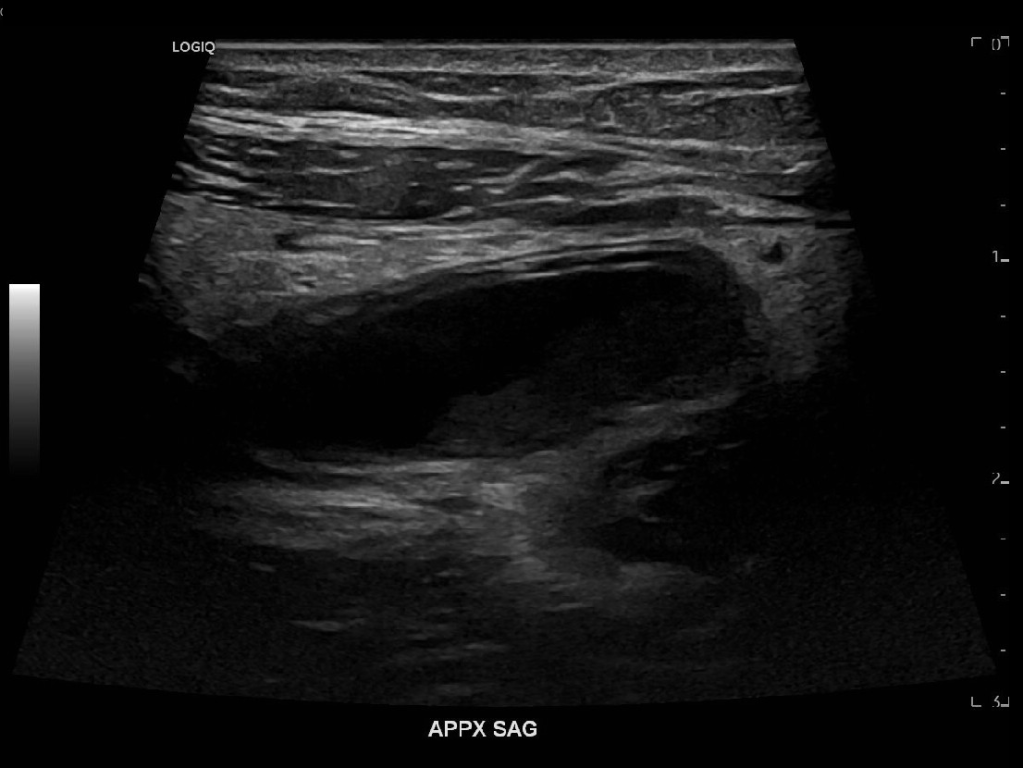

Appendicitis 13

Acute appendicitis @ 1 cm with L2-9mhz and L6-24mhz transducer GE Logiq e10.